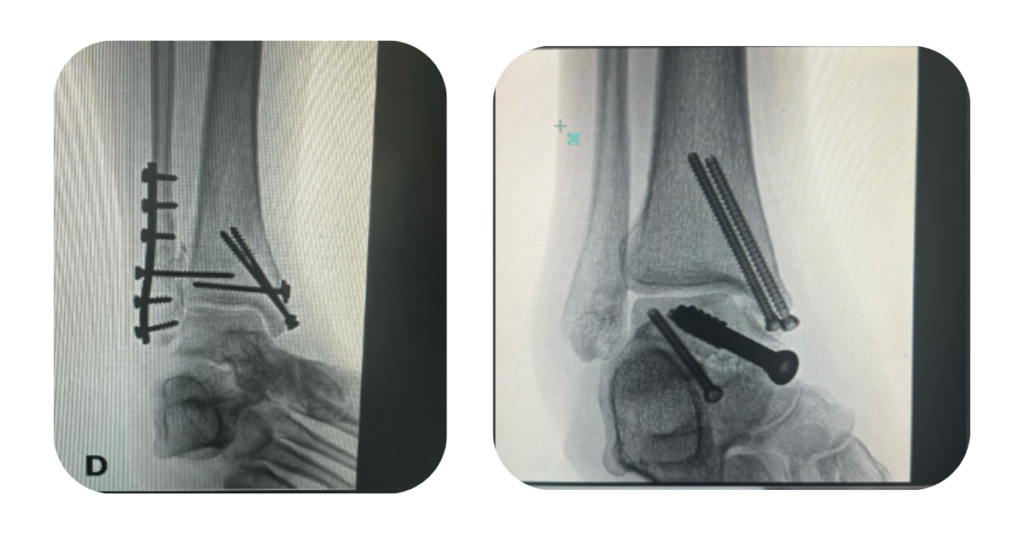

Quebrei o Tornozelo: E Agora? Tudo Sobre a Cirurgia e o Retorno às Atividades

Fraturar o tornozelo é algo que pode acontecer em uma simples torção, queda, acidente ou durante a prática esportiva. Além da dor intensa e do inchaço imediato, uma pergunta comum surge logo após o diagnóstico: “vou precisar de cirurgia?” Neste artigo, explicamos de forma clara quando a cirurgia é necessária, como ela é realizada e […]